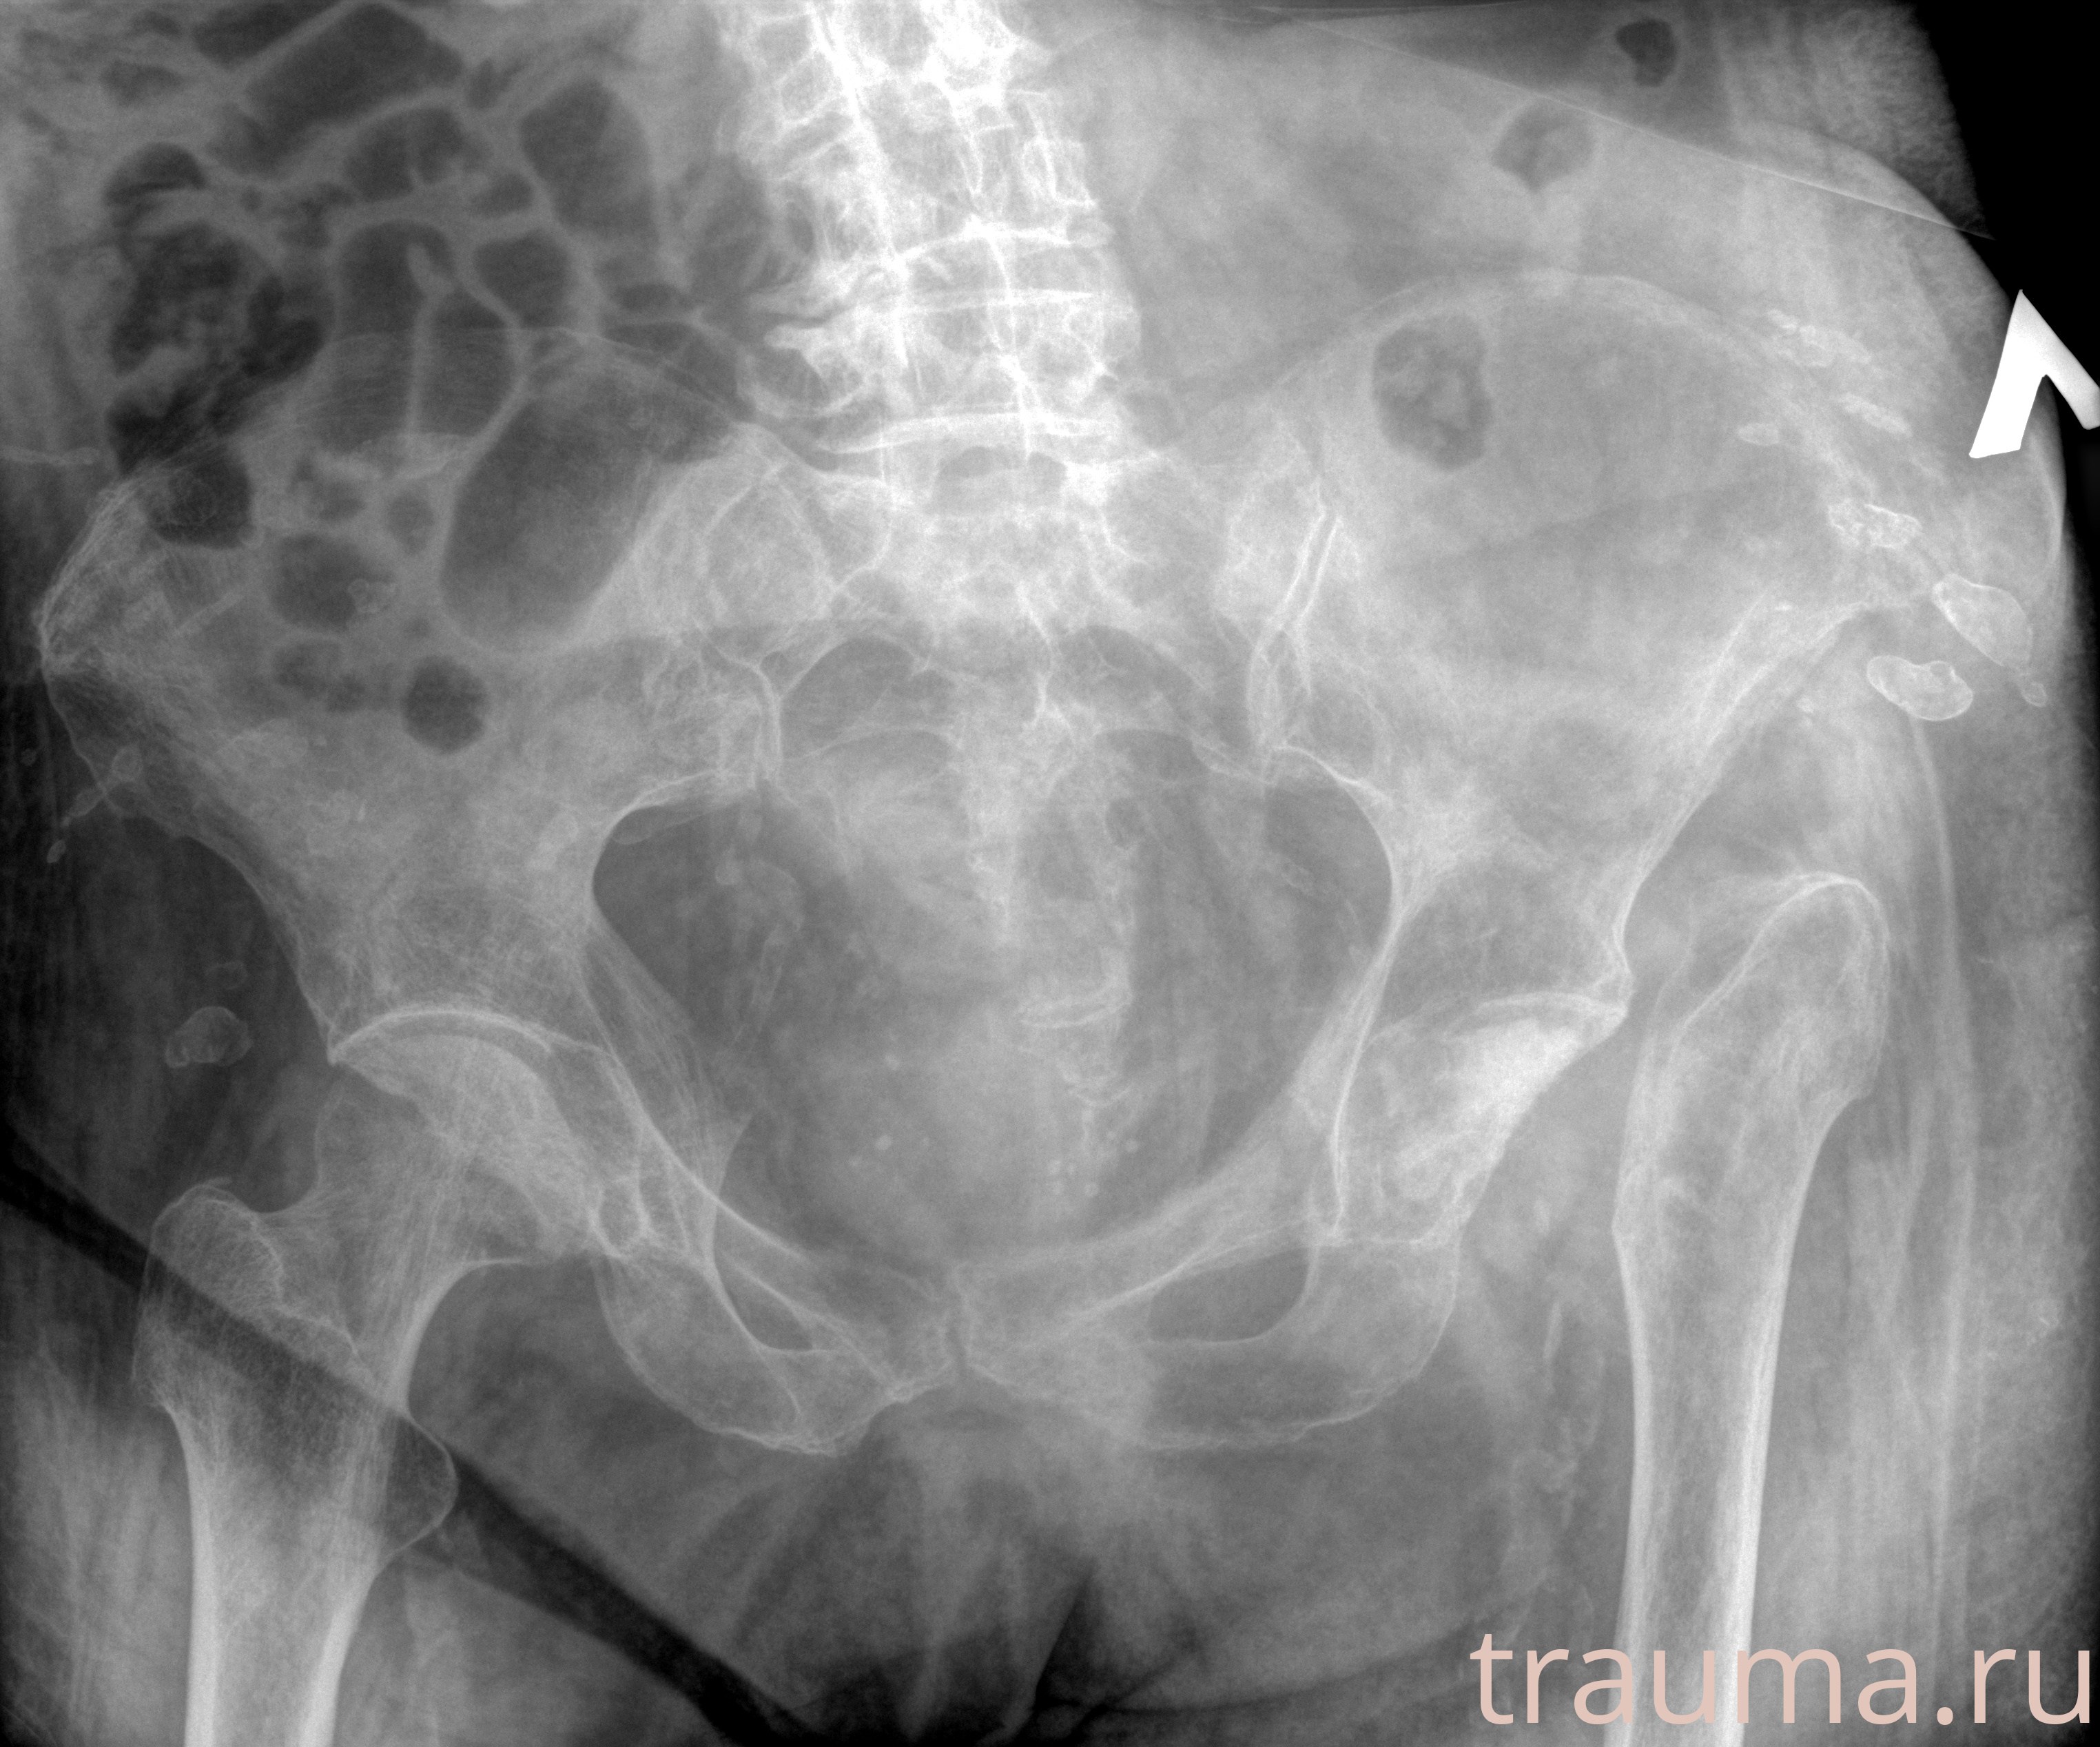

Первая помощь при переломе шейки бедра

Рентгенограммы

Рентген на дому: по вашему адресу приезжает врач-рентгенолог, травматолог-ортопед с мобильным рентгеновским аппаратом, проводит диагностику травмы или заболевания, делает необходимые рентгенограммы, дает рекомендации по дальнейшему лечению. Получить качественные снимки в домашних условиях возможно благодаря уникальной методике, разработанной МосРентген Центром для института  Склифосовского